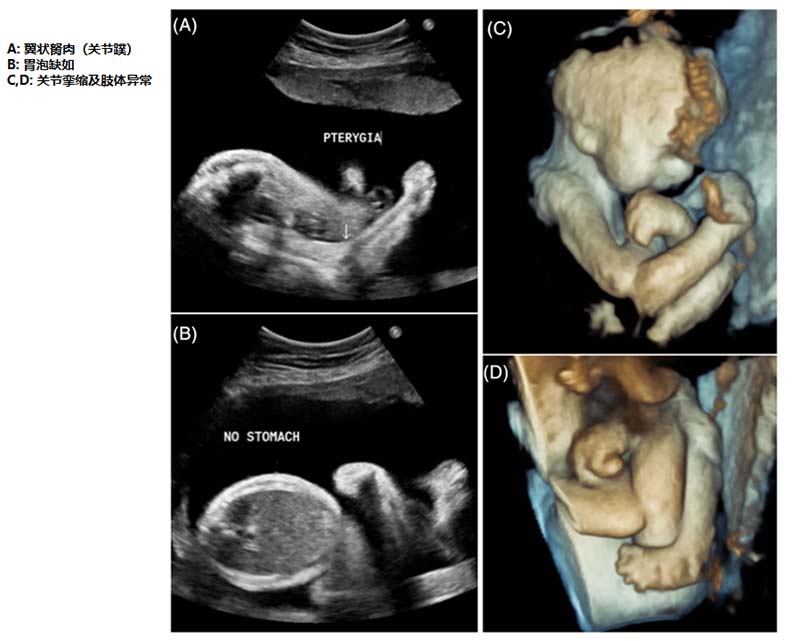

图2.妊娠27周+6天时进行的胎儿超声检查